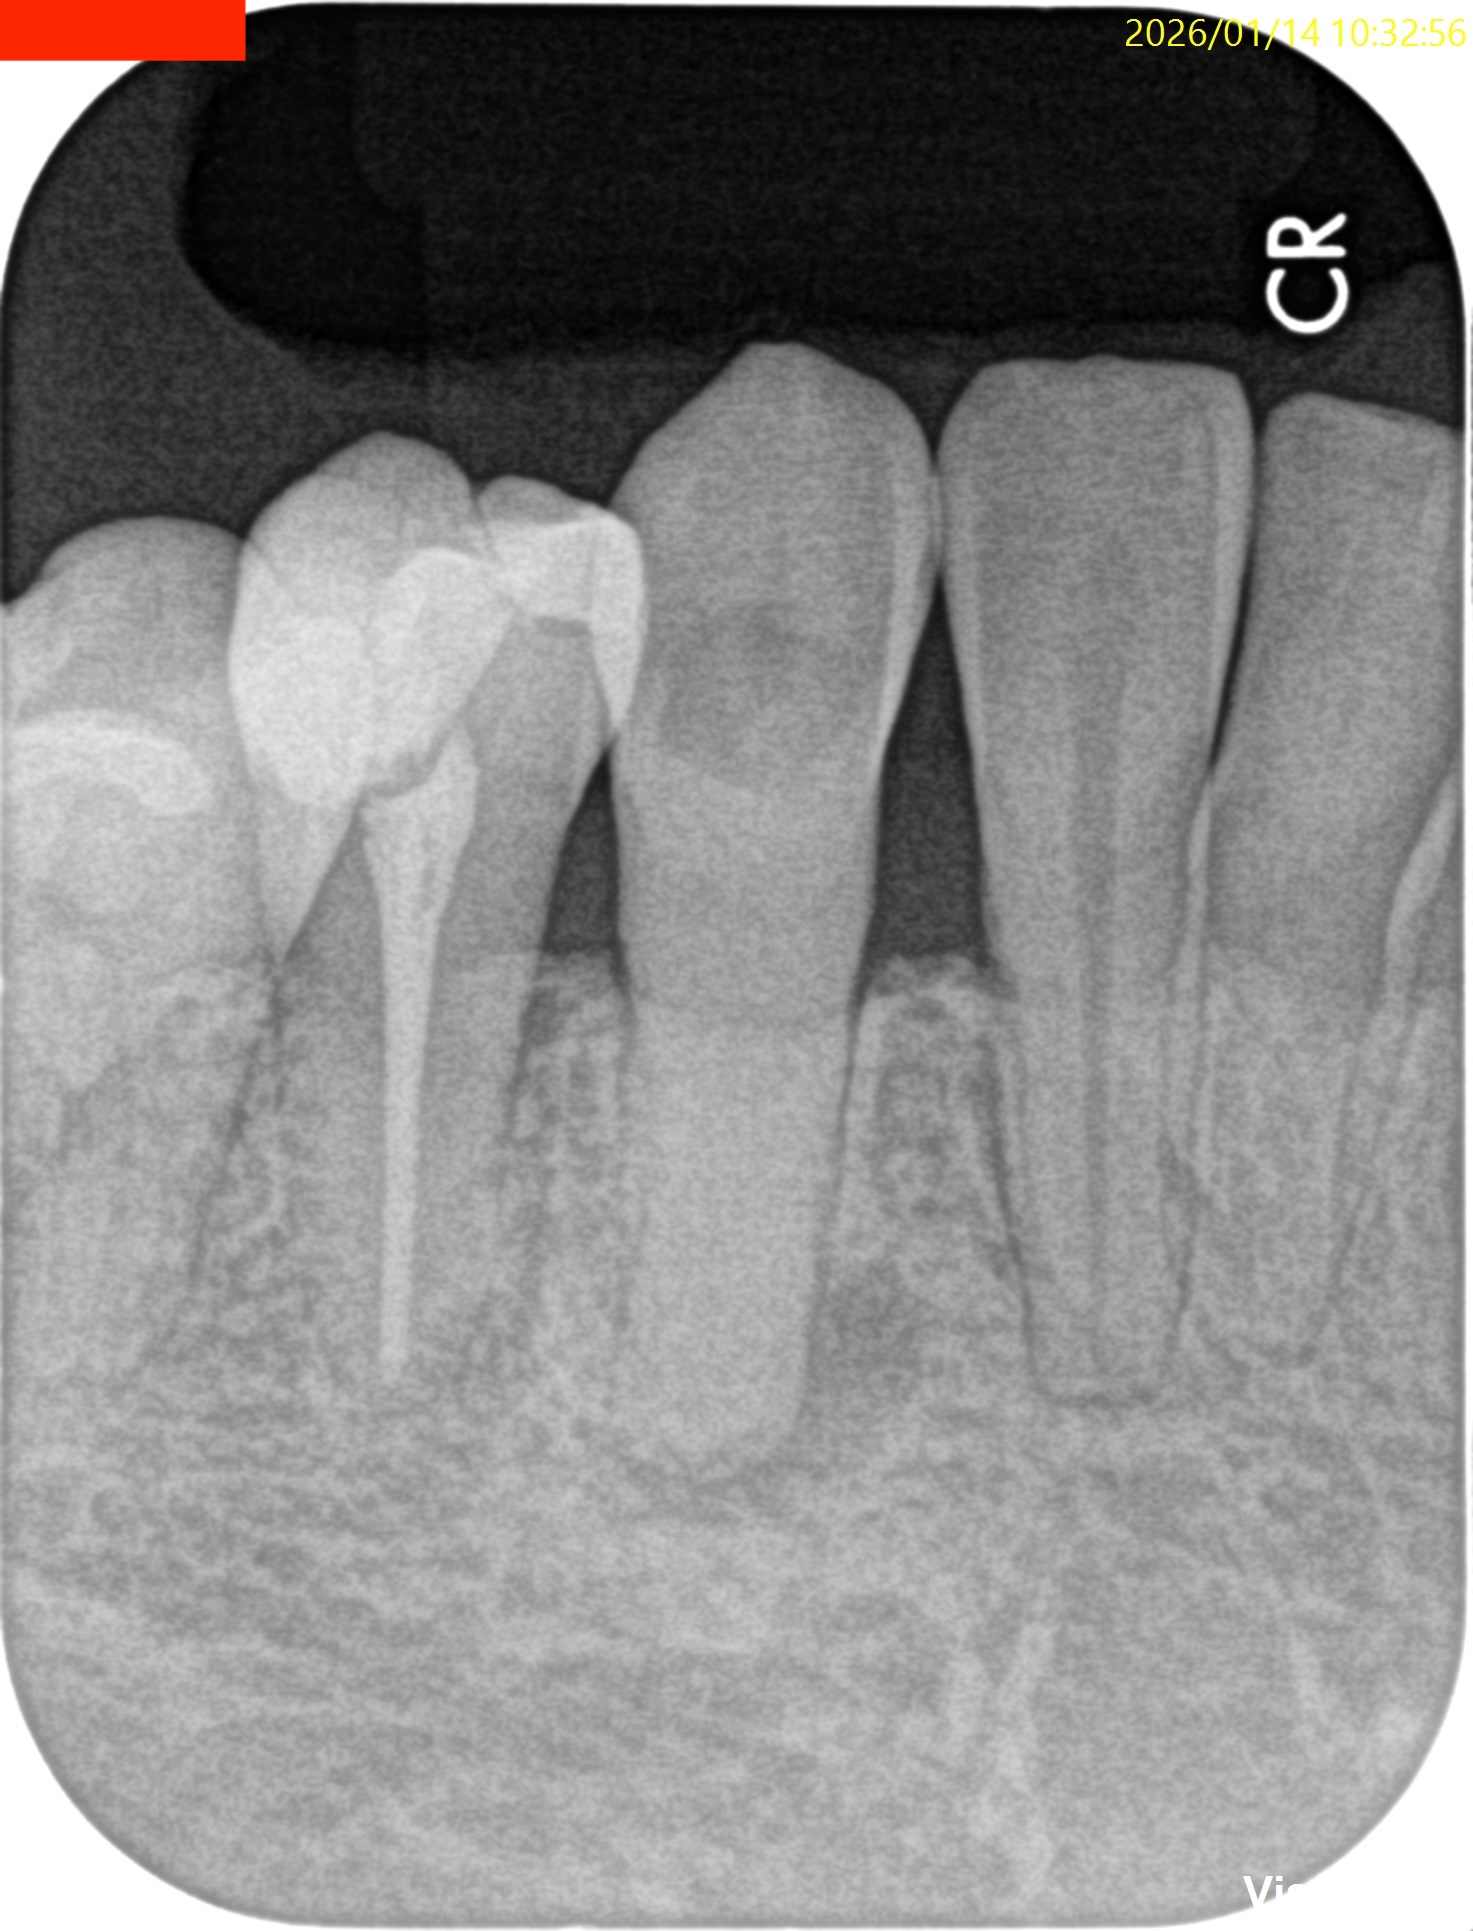

Pre-op Endo test(2026.1.14)

iphoneが就寝前に歯に落ちてきたという。

さておき、外傷が歯に起きると歯髄のある根管が石灰化する。

これで根管治療ができるだろうか?

根管治療だがCBCTによれば、

切端からApexまで約25mmだ。

切端を削れば露髄するはず?である。

が、根管は硬かった…。。。